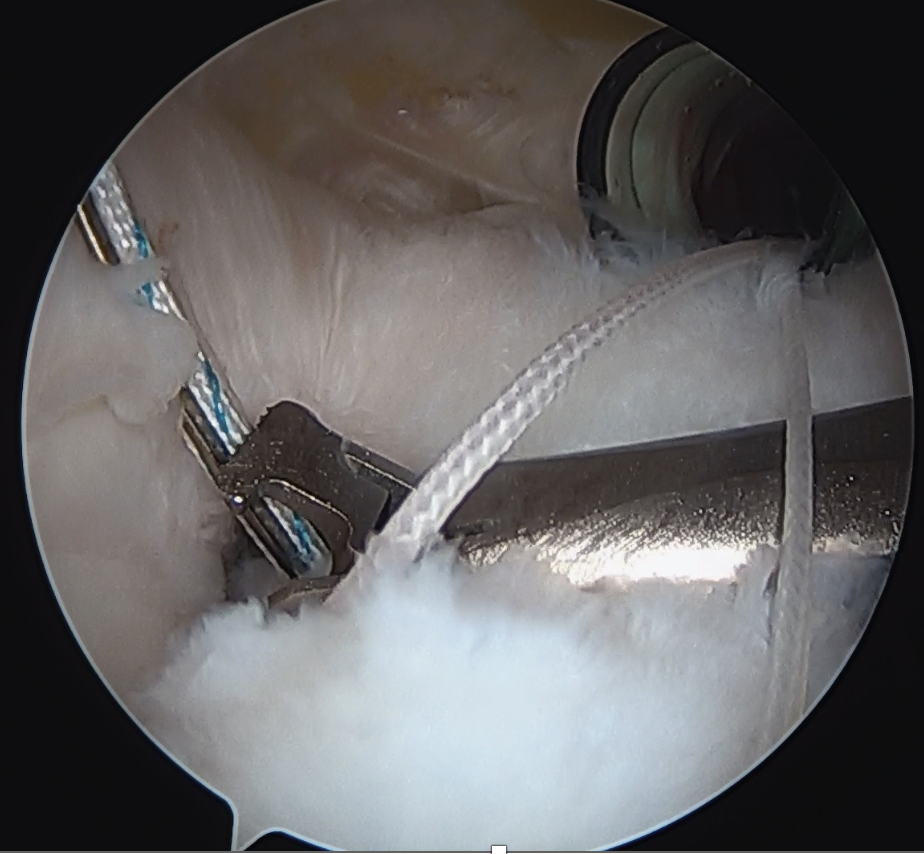

Medial row anchors

- inserted through additional stab incision for suture management

- just medial to articular cartilage

Pass sutures through medial cuff tendon

- camera posterior

- suture passer via lateral portal

- retrieve sutures through anterior portal

- repeat

- tie medial row